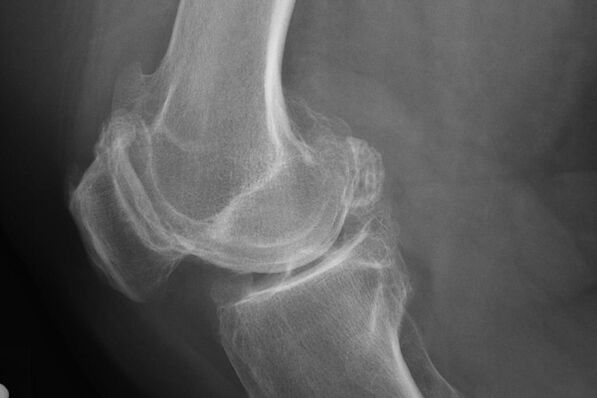

X -Ray bakal ngabantosan ngaidentipikasi percikan dina rawan.

Saatos ujian, dokter anu resep skorografi pasien. Ieu mangrupikeun metodeu utama diagnosis arthrosis of dengkul tina gelar naon waé.

X -ray masihan dokter ideu ngeunaan parobahan dina karpét dina tulang gabungan. Nanging, dina sababaraha kasus, tahap awal moal dihartikeun gambar.

Upami diperyogikeun, dokter tiasa resep petikan ulang anu diulang hiji sinar x atanapi tomonsesies résiko sareng nagnana.